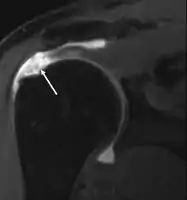

Diagnostic modalities, dependent on circumstances, include X-ray, MRI, MR arthrography, double-contrast arthrography, and ultrasound. Although MR arthrography is currently considered the gold standard, ultrasound may be most cost-effective.[34] Usually, a tear will be undetected by X-ray, although bone spurs, which can impinge upon the rotator cuff tendons, may be visible.[35] Such spurs suggest chronic severe rotator cuff disease. Double-contrast arthrography involves injecting contrast dye into the shoulder joint to detect leakage out of the injured rotator cuff,[36] and its value is influenced by the experience of the operator. The most common diagnostic tool is magnetic resonance imaging (MRI), which can sometimes indicate the size of the tear, as well as its location within the tendon. Furthermore, MRI enables the detection or exclusion of complete rotator cuff tears with reasonable accuracy and is also suitable for diagnosing other pathologies of the shoulder joint.[37]

MRI

Magnetic resonance imaging (MRI) and ultrasound[46] are comparable in efficacy and helpful in diagnosis, although both have a false positive rate of 15–20%.[47] MRI can reliably detect most full-thickness tears, although very small pinpoint tears may be missed. In such situations, an MRI combined with an injection of contrast material, an MR-arthrogram, may help to confirm the diagnosis. It should be realized that a normal MRI cannot fully rule out a small tear (a false negative) while partial-thickness tears are not as reliably detected.[48] While MRI is sensitive in identifying tendon degeneration (tendinopathy), it may not reliably distinguish between a degenerative tendon and a partially torn tendon. Again, magnetic resonance arthrography can improve the differentiation.[48] An overall sensitivity of 91% (9% false negative rate) has been reported, indicating that magnetic resonance arthrography is reliable in the detection of partial-thickness rotator cuff tears.[48] However, its routine use is not advised, since it involves entering the joint with a needle, with the potential risk of infection. Consequently, the test is reserved for cases in which the diagnosis remains unclear.